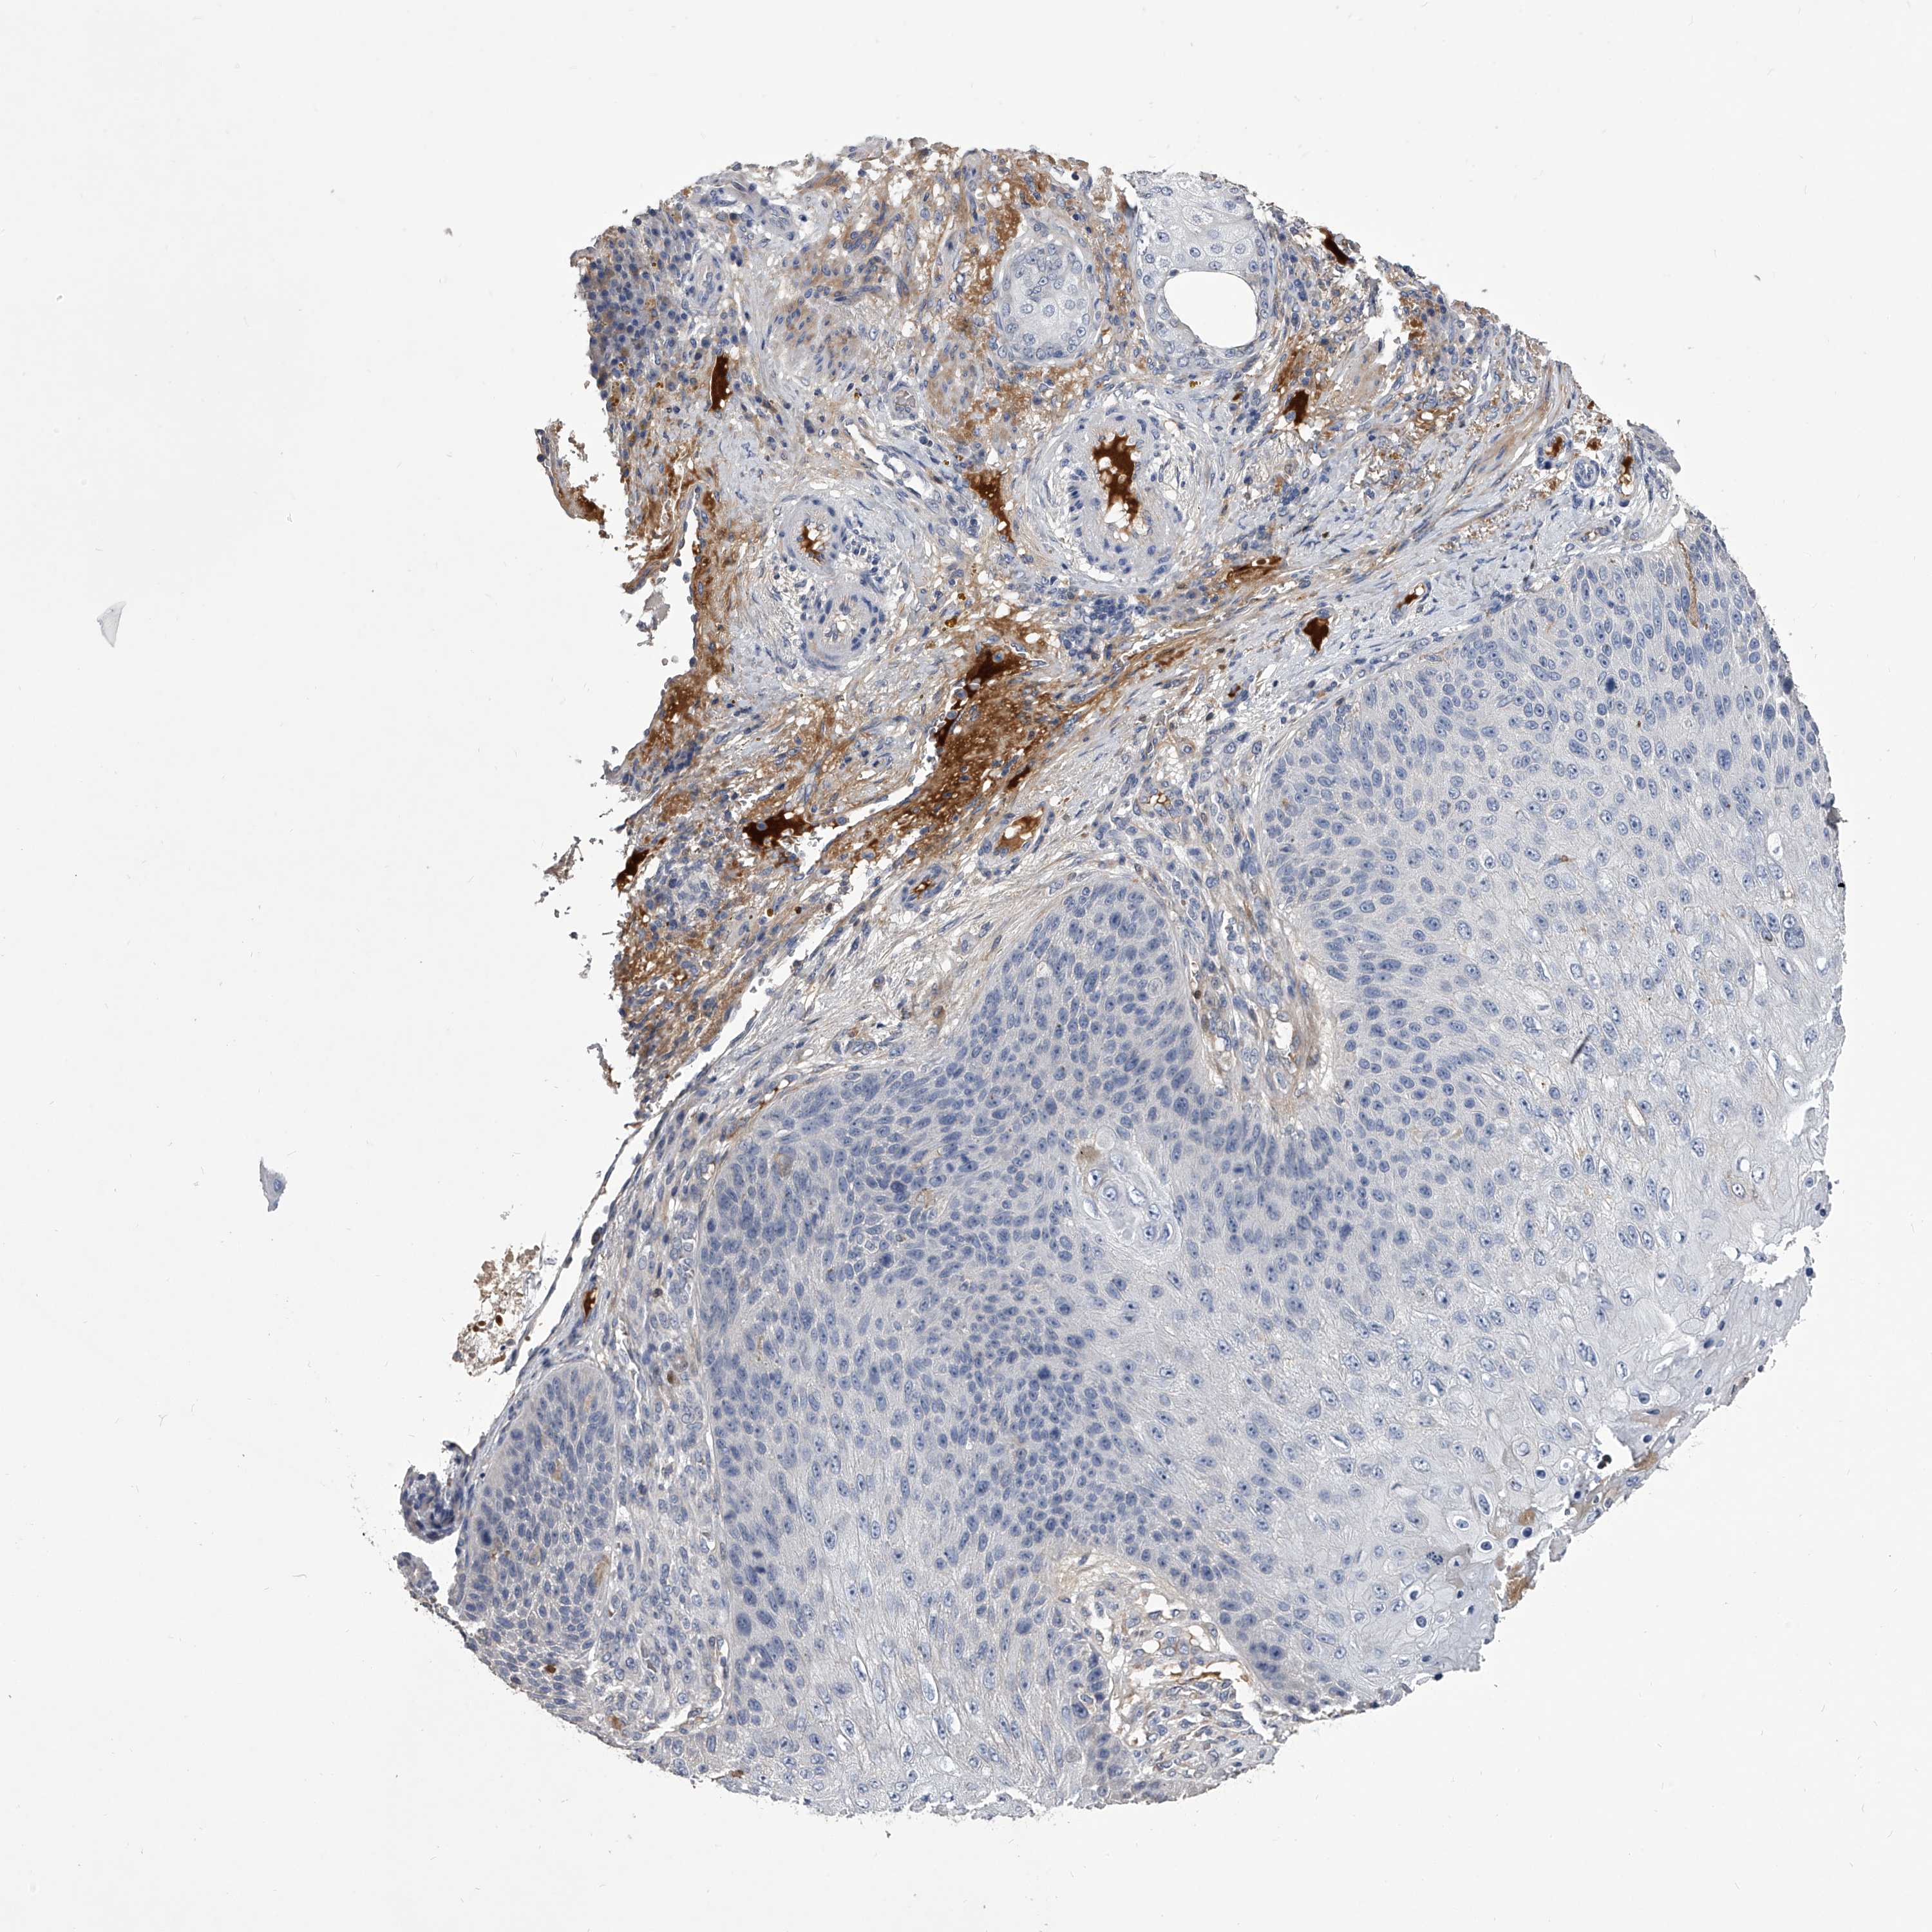

SKIN CANCER - Protein expressioni

A mouse-over function shows sample information and annotation data. Click on an image to view it in a full screen mode. Samples can be filtered based on level of antibody staining by selecting one or several of the following categories: high, medium, low and not detected. The assay and annotation is described here.

Each image is clickable and will lead to virtual microscopy that enables deeper exploration of all samples and also displays staining intensity scores, fraction scores and subcellular localization as well as patient and tissue information for each sample.

Antibody HPA029666

Antibody HPA029667

Antibody HPA029668

Antibody HPA029669

Staining

High

Medium

Low

Not detected

Basal cell carcinoma

Squamous cell carcinoma, NOS

Squamous cell carcinoma, metastatic, NOS